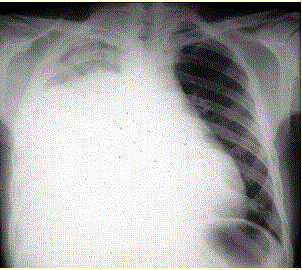

患者男,34岁。进行性胸闷、气促1个月余,伴有干咳、右胸隐痛以及消瘦,无咯血、发热、盗汗、潮热等。(提示 胸部X线检查如图所示。)考虑患者目前出现...

问题 患者男,34岁。进行性胸闷、气促1个月余,伴有干咳、右胸隐痛以及消瘦,无咯血、发热、盗汗、潮热等。(提示 胸部X线检查如图所示。) 考虑患者目前出现的情况是(提示 为解决患者胸闷、气促症状,给予胸腔插管引流胸腔积液,一次性放出淡黄色胸腔积液约1 800 ml。患者引流后自觉气促症状减轻,但半小时后渐觉胸闷、呼吸困难再次加重,剧咳伴咳大量泡沫样痰。体格检查:端坐呼吸,口唇发绀,双肺满布湿性啰音,心率130次/min,律齐。)

选项 A.急性肺血栓栓塞症 B.急性呼吸窘迫综合征 C.肺复张后肺水肿 D.胸膜反应 E.医源性气胸 F.急性左心衰竭 G.胸腔内出血

答案 C